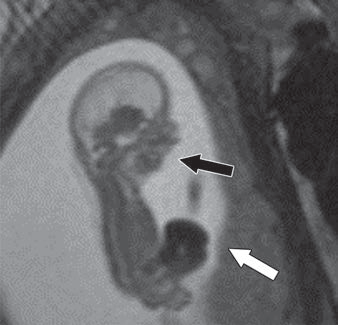

True vs. False Lumen in Acute Aortic Dissection

Look for the beak sign and larger caliber to ID the false; check the arch “wraparound” and calcification patterns for truth.